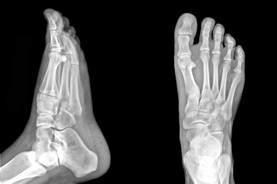

The Foot Institute is an association of Grande Prairie Doctors specializing in the medical treatment of the foot and ankle, and is one of the largest groups of foot specialists in Alberta.

The Grande Prairie Foot Institute is dedicated to the medical and surgical treatment of the foot. Our mandate is to provide the best possible medical, surgical and preventative treatment available for our patients. We do this by providing well-trained Doctors who are committed to treat and prevent all types of foot pain, biomechanical disorders, as well as all other problems relating to the feet.

At the Grande Prairie Foot Institute, our Doctors are trained to specifically treat problems associated with your feet or ankles. Below are several of the most common problems that we see on a day to day basis: